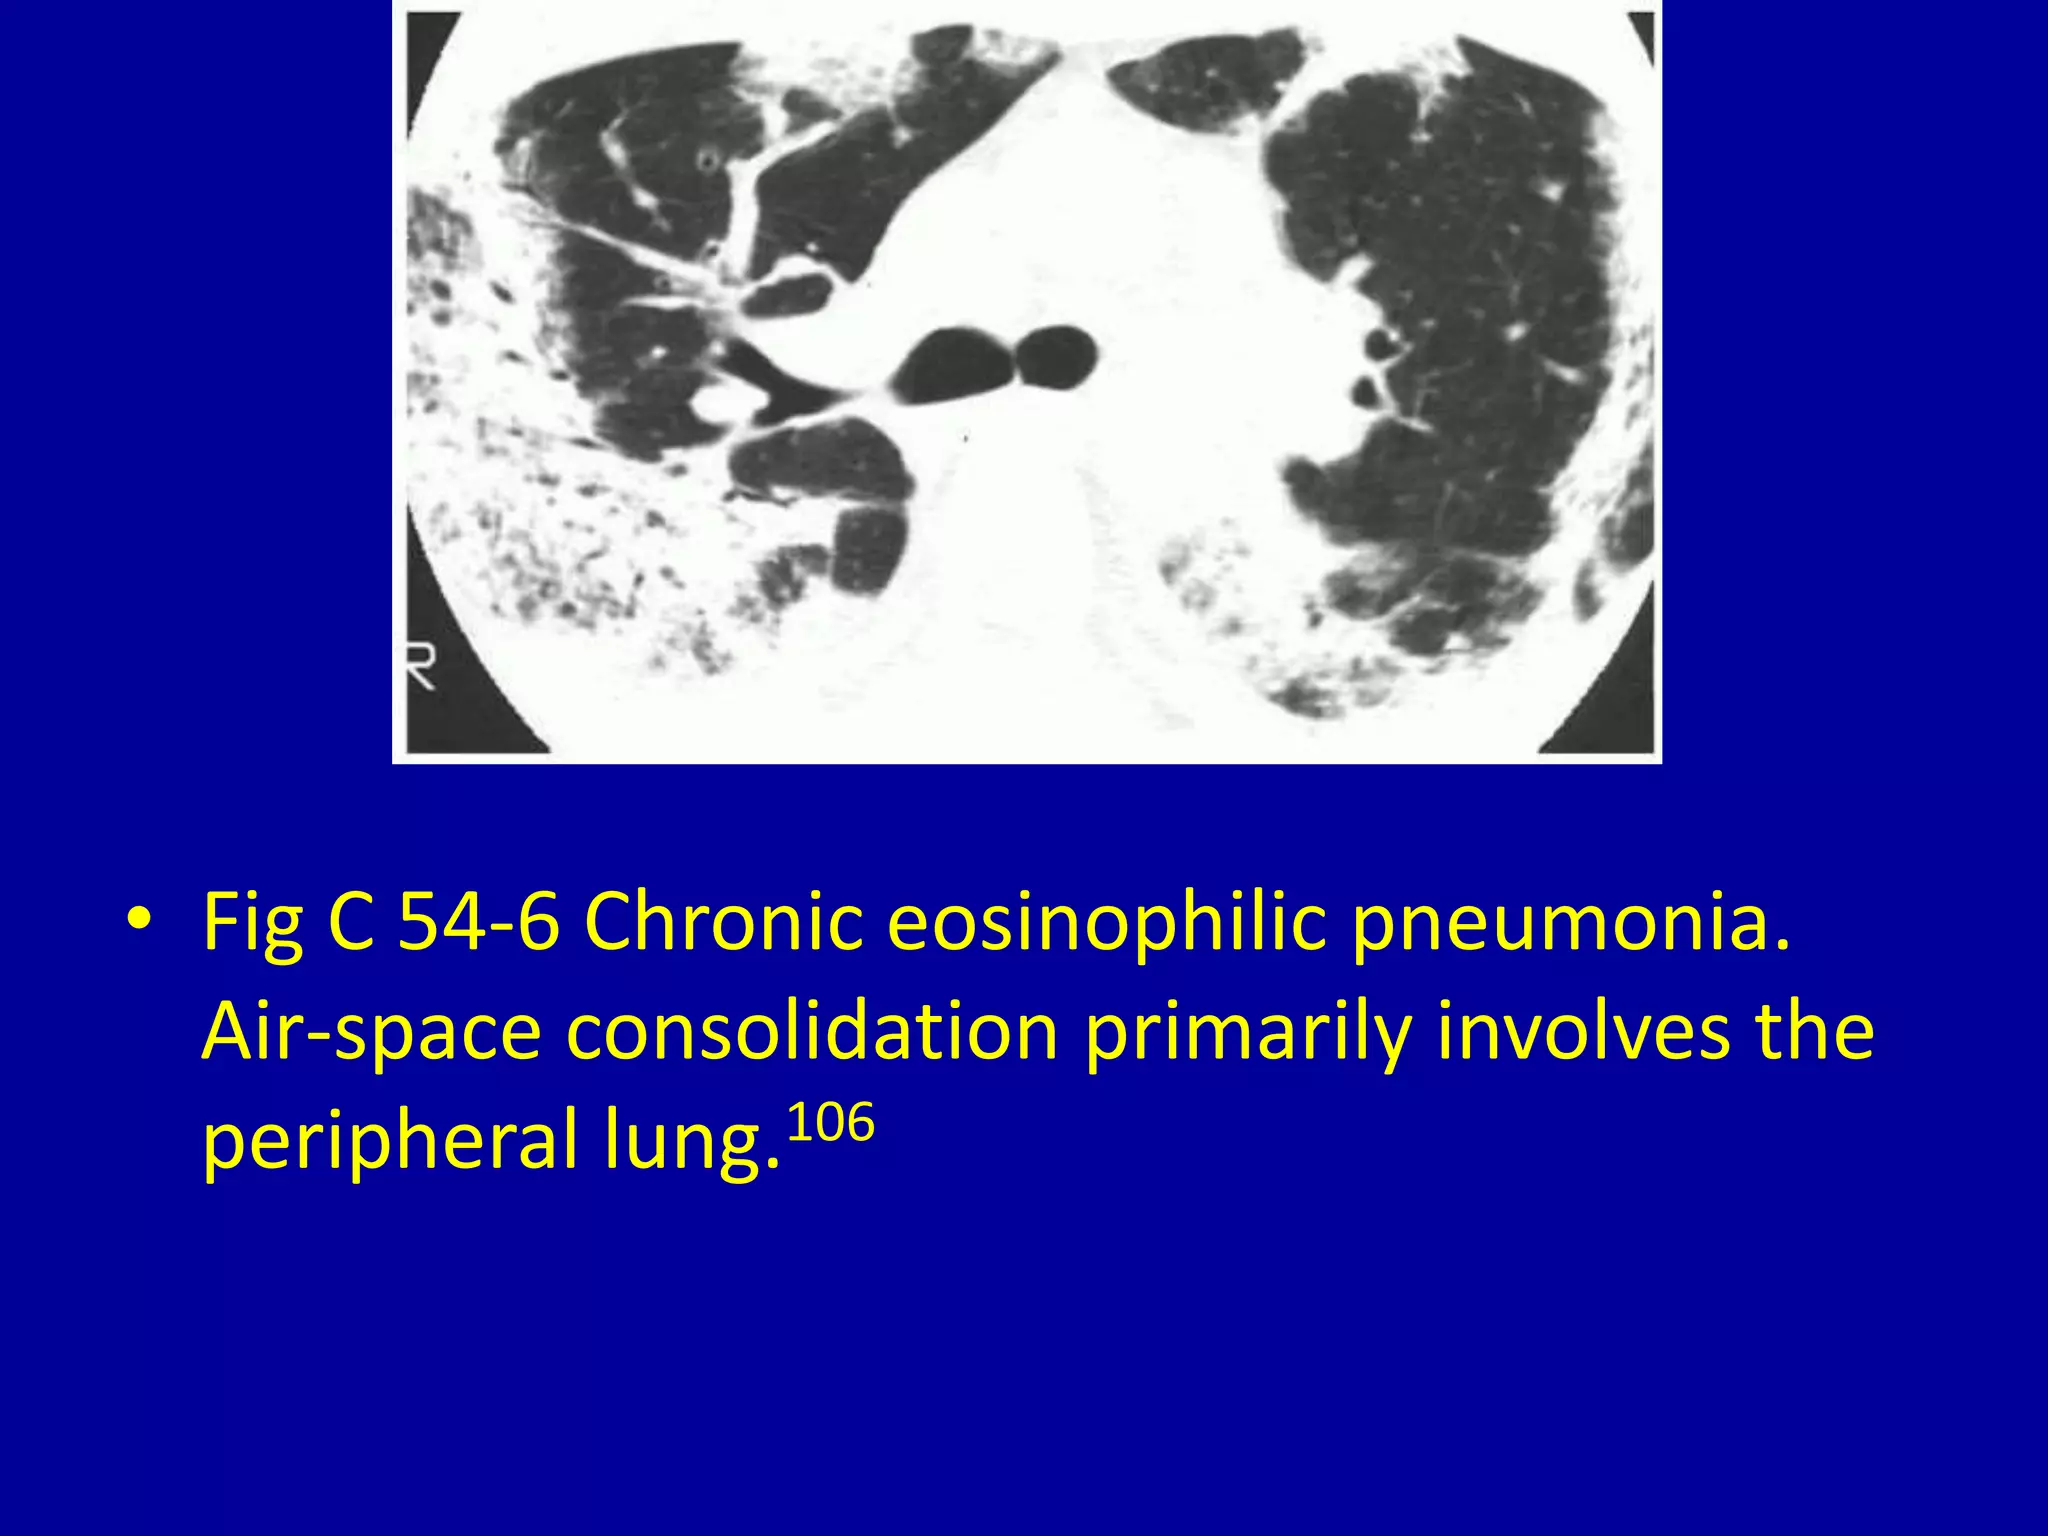

This document discusses various pulmonary diseases that predominantly affect the upper zones of the lungs. It includes 10 figures showing CT scan findings of different conditions like postprimary tuberculosis, sarcoidosis, pulmonary Langerhans cell histiocytosis, silicosis, centrilobular emphysema, chronic eosinophilic pneumonia, cystic fibrosis, allergic bronchopulmonary aspergillosis, neurogenic pulmonary edema, and ankylosing spondylitis. The images demonstrate lesions, nodules, consolidations, cysts, and other abnormalities that are largely limited to the upper lobes and regions of the lungs.